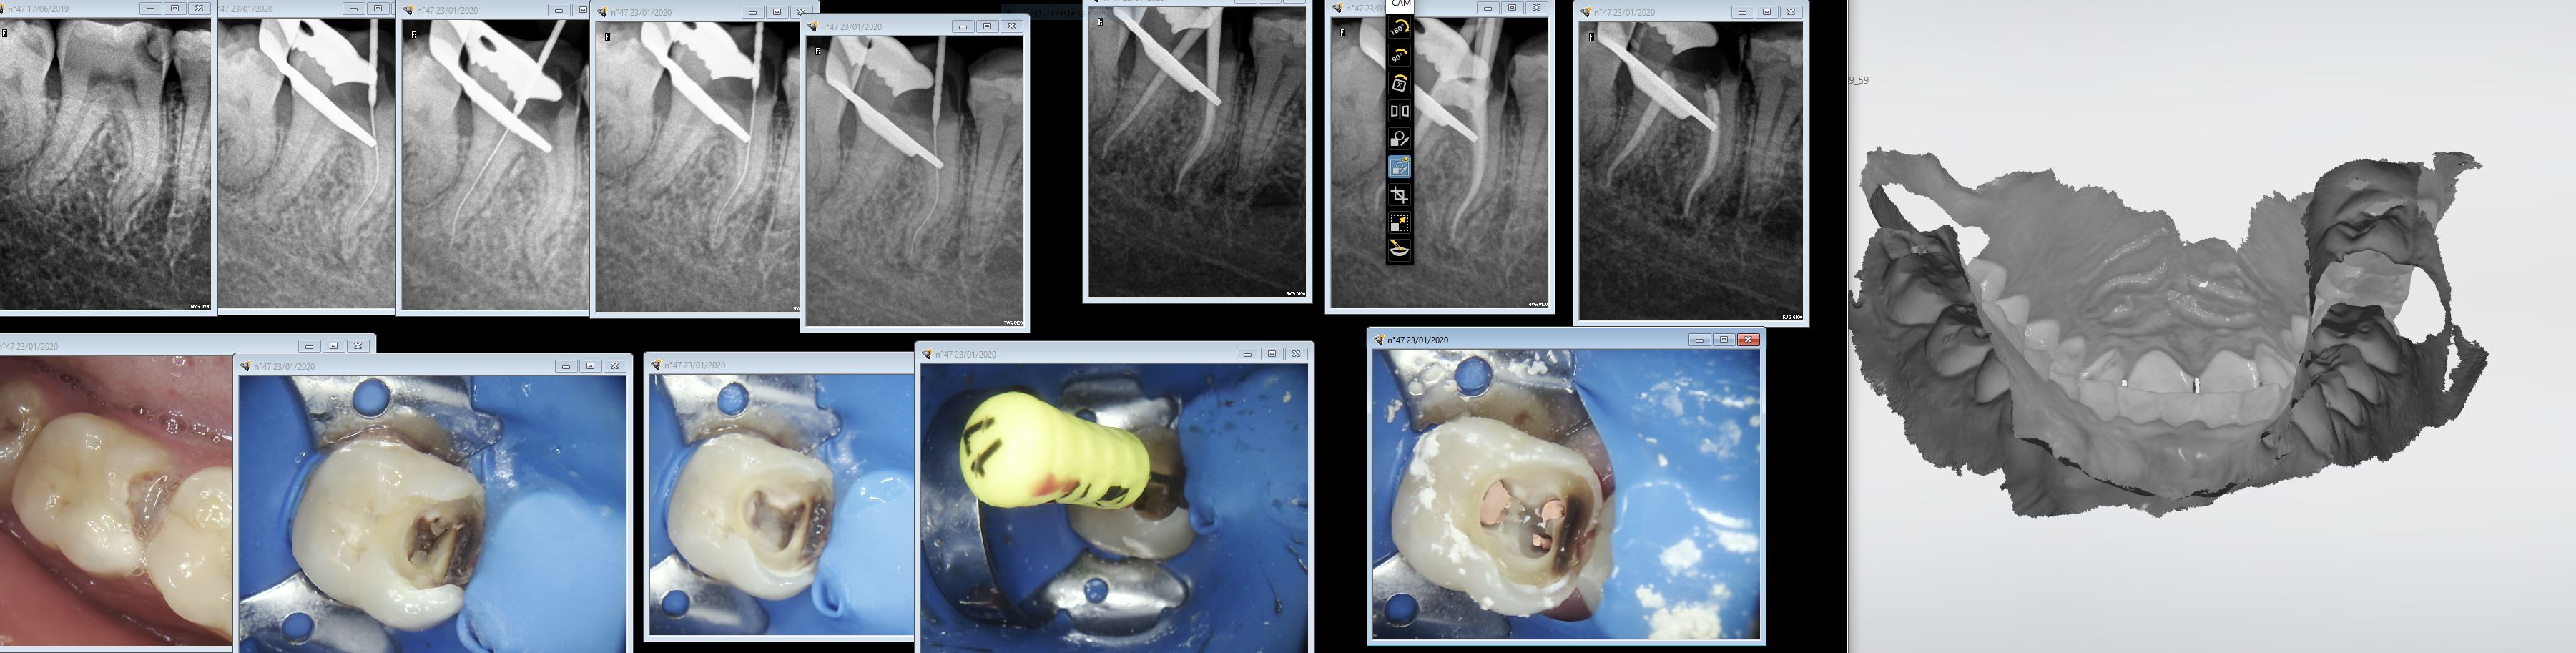

Endo 47 1 mfqykt - Eugenol

4a338550 6a5b 47ea b2a7 d3cb675c5076 oni5gh - Eugenol

fistule 69

25/01/2020 à 14h19